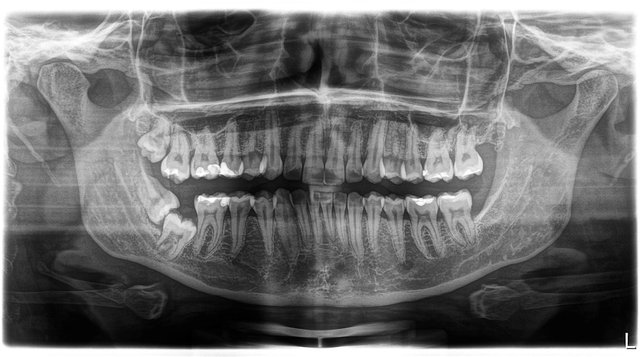

Panorama-Übersichtsaufnahme

Orthopantomographie (OPT)